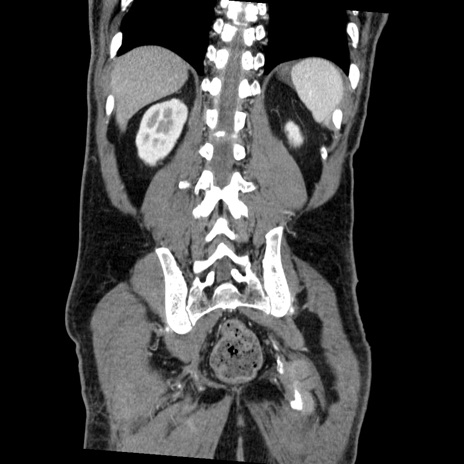

症例22(冠状断像)

【症例】50歳代男性

【主訴】腹痛

【現病歴】AVMからの被殻出血のため回復期リハ病棟入院中。 本日午後3時頃急に下腹部痛が出現した。

【既往歴】AVM、被殻出血、虫垂炎、高血圧

【身体所見】意識晴明、左半身不全麻痺、会話の理解は良好、36.5°C、腹部:膨隆、全体に板状硬、下腹部正中に圧痛点あり、反跳痛-、筋性防御不明、右下腹部にope scar

【データ】WBC 9400、CRP 0.06